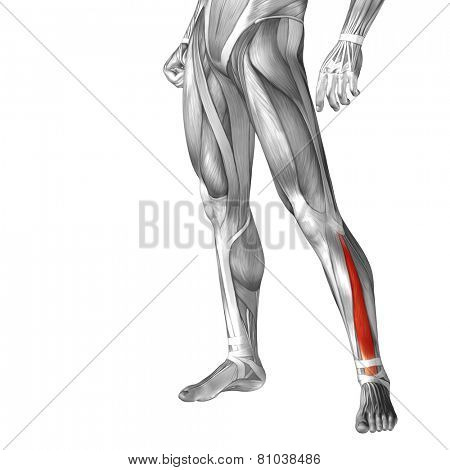

Extensor